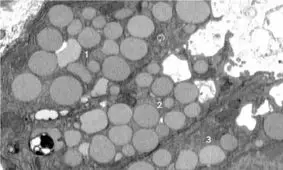

• یک مطالعه جدید نشان می‌دهد که سلول‌ها برای التیام و جوان شدن دوباره، مواد زائد درون خود را استفراغ می‌کنند.